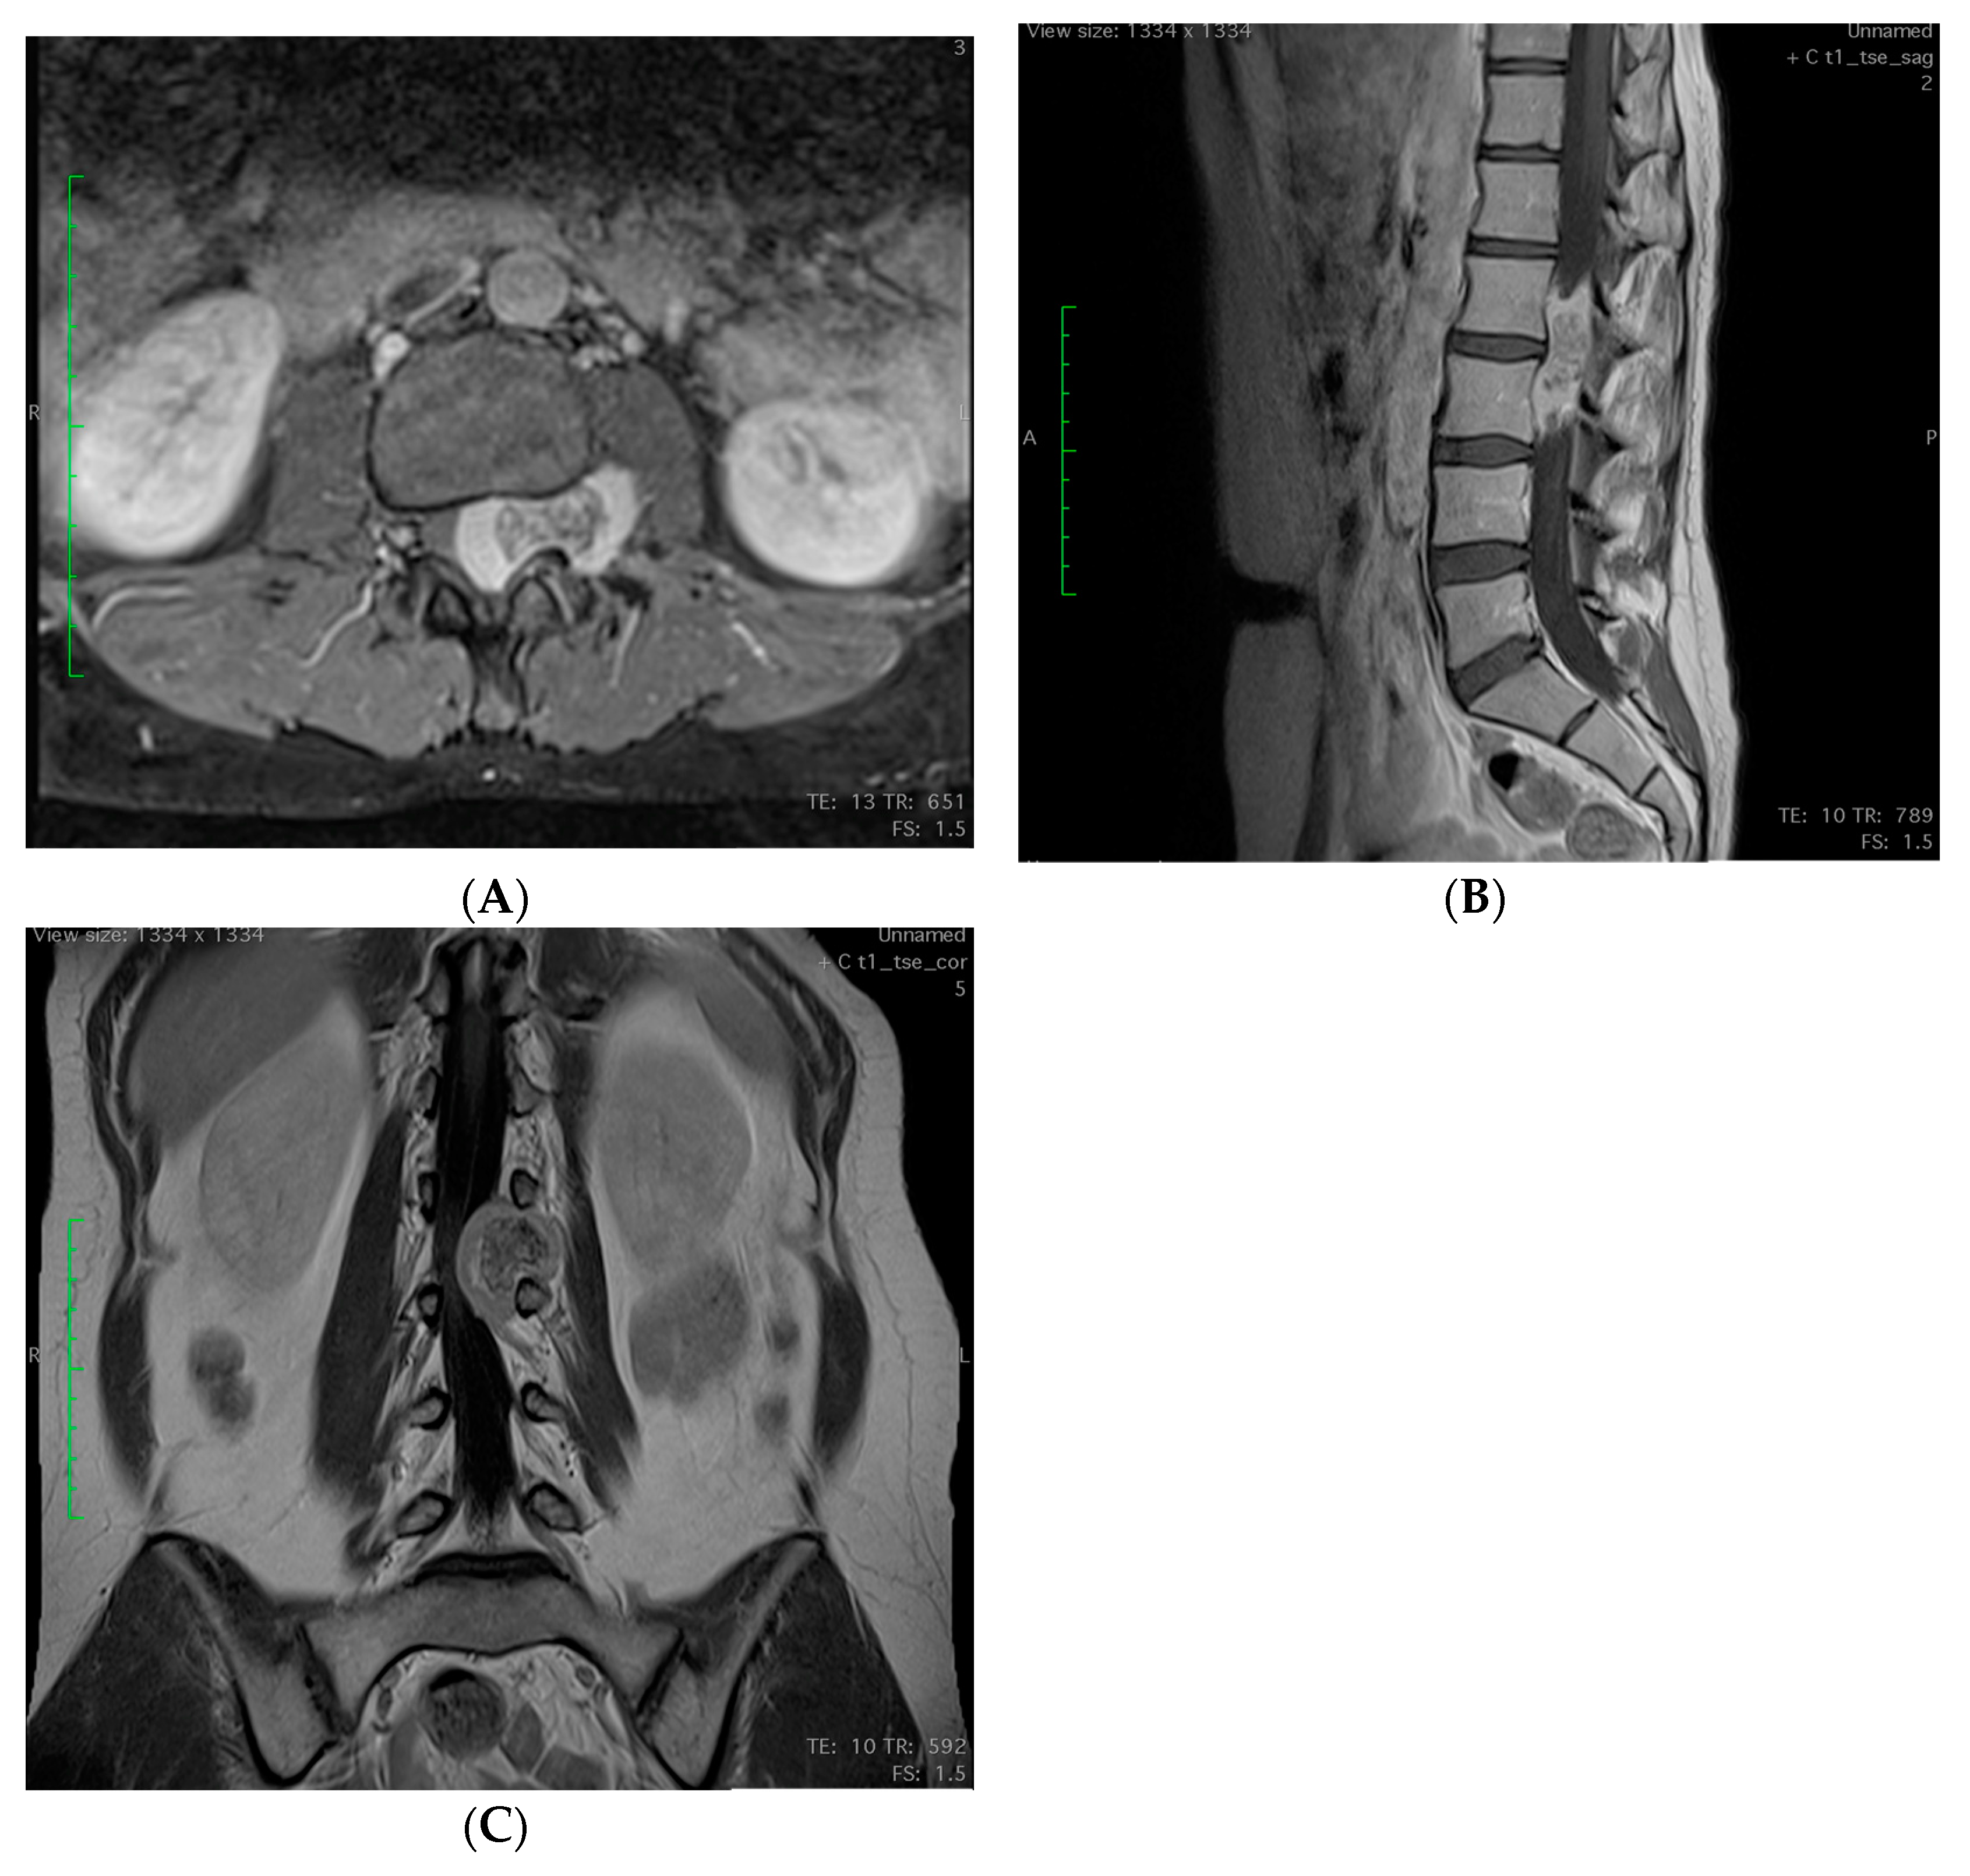

2.3. Imagining